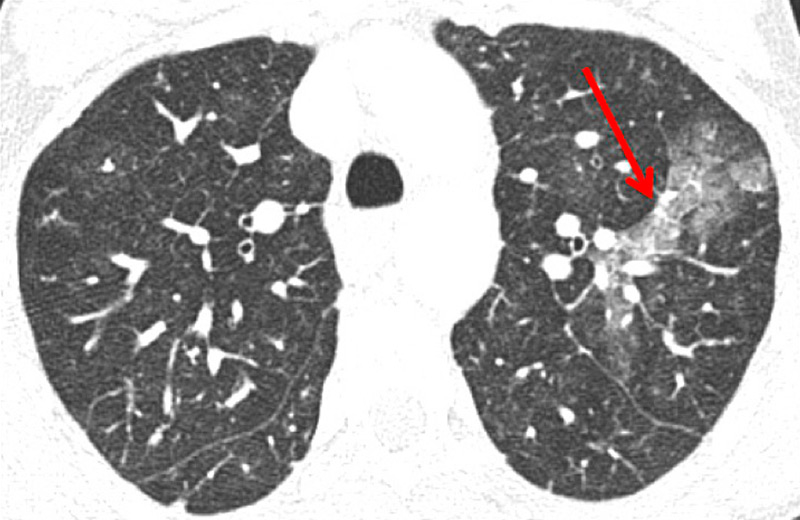

Nowadays, DECT imaging can be used for pathologies other than CTEPH and seems to offer advantages for PH characterisation because different DECT findings have been described in acute pulmonary embolism, CTEPH and idiopathic PAH (IPAH). In fact, perfusion defects are smaller and less defined in PAH than in CTEPH. This is likely due to focal under- and overperfusion as a result of the structural pulmonary vascular changes that occur in PH, which include vascular endothelial damage, cellular proliferation and occlusion in the distal pulmonary vasculature. Perfusion heterogeneities in DECT imaging are also common and seen in most cases of PAH. Findings of perfusion inhomogeneities related PAH have long been recognised in scintigraphy, and often are referred to as having a “mottled” pattern [42]. These perfusion defects are different from those seen in CTEPH, with nonsegmental and poorly defined defects (fig. 5). This heterogeneity is related to the severity of the disease. In PAH, this perfusion variability on scintigraphy is well correlated with pulmonary vascular resistance, as Talwar et al. showed [43]. Recently, similar results were published for DECT techniques (fig. 6). Ameli-Renani et al. described an increased enhancement of pulmonary arteries with reduced iodine lung perfusion in PH, and a good correlation of DECT perfusion heterogeneities with pulmonary vascular resistance; they showed a greater heterogeneity in parenchymal iodine maps in PH without pulmonary embolism [13]. The authors concluded that perfusion heterogeneities seen in DECT appear to be a direct reflection of pulmonary vascular resistance.

Figure 5

Difference of perfusion defects in pulmonary hypertension depending on the aetiology: triangular well-defined defect seen in chronic thromboembolic pulmonary hypertension (A) and poorly defined defect with mottled pattern seen in idiopathic pulmonary arterial hypertension (B).